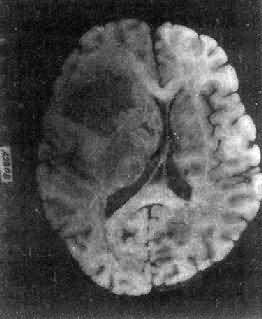

图16-26 髓母细胞瘤 瘤细胞较小,着色深,密集排列,有菊形团形成 髓母细胞瘤恶性程度高,预后差。 (三)脑膜瘤 脑膜瘤(meningioma)可来源于脑膜的各组成成分如蛛网膜细胞,纤维母细胞或血管,其中多数来源于蛛网膜颗粒中的蛛网膜细胞。本瘤大多生长缓慢,良性类型可完全无症状,在70岁以上老人的尸检中,发现无症状的脑膜瘤不在少数,无症状脑膜瘤占颅内肿瘤的14%。脑膜瘤患者多为40~50岁中年人,女性较男性多。 肿瘤的好发部位与蛛网膜颗粒所在部位相同,常见于上矢状窦旁大脑镰两侧,蝶骨嵴,嗅沟,小脑脑桥角;在脊髓则以胸段为多见,一般颅内脑膜瘤较脊髓脑膜瘤多2倍。 肉眼观,肿瘤呈球形,分叶状或不规则形,质实或硬,边界清楚,周围脑组织受压成凹陷切迹(图16-27)。少数肿瘤呈斑块状覆盖较广泛区域,甚至整个脑半球,称为斑块型脑膜瘤。肿瘤质地硬,切面灰白色,呈颗粒状、条索旋涡状,有的质地似砂砾样,乃由于有多量砂粒体存在。

图16-27 脑膜瘤 于大脑两半球间有一近似球形肿瘤,边界清楚,周围脑组织受压萎缩 由于脑膜瘤的组织来源复杂,其组织学图像也可呈现下列基本类型: (1)脑膜细胞型(融合细胞型):瘤细胞胞浆丰富,边界不清楚,胞核椭圆形,细胞排列呈分叶状或旋涡状,为纤维间质条索所分隔。 (2)纤维细胞型:瘤细胞呈长梭形,排列成致密的交织束状结构,其间有网状纤维及胶原纤维,有时胞核呈栅状排列。 (3)过度(混合)型:脑膜细胞与纤维细胞混合,排列成分叶状,中央为脑膜细胞,周围为纤维细胞,常形成旋涡状结构(图16-28),其中常包含有同心层状结构的砂粒体,乃变性肿瘤细胞及钙盐沉积。肿瘤质地硬,似砂砾状。

图16-28 脑膜瘤 瘤细胞为圆形或多角形,作旋涡状排列 (4)血管母细胞型:肿瘤细胞丰富,胞浆模糊,胞核椭圆,多排列在毛细血管旁,并有较多的网状纤维。 各型脑膜瘤中均可有不同程度的出血、钙化,有些并有黄色瘤细胞、软骨、骨、黑色素及粘液样变。 大多数脑膜瘤为良性,瘤细胞可引起邻近颅骨的骨质增生,或肿瘤浸润,但不引起广泛播散或转移,也不侵入邻近的神经组织。一般手术后复发率可达15%,其中血管母细胞型有复发和播散倾向,预后较差。少数脑膜瘤细胞间变明显,与梭形细胞肉瘤难以区分,可发生颅外转移,主要累及肺及淋巴结。